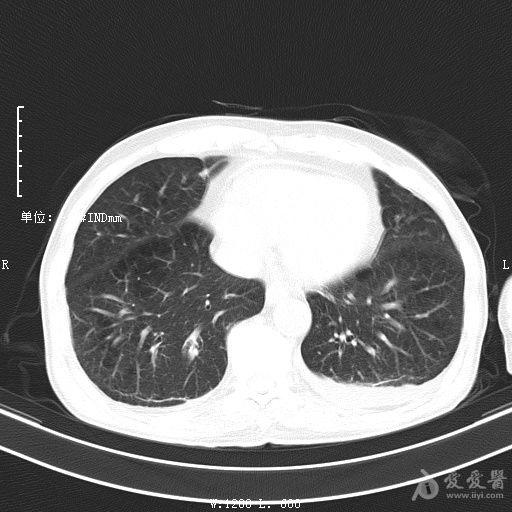

最新的肺炎疫情形勢嚴峻,病毒變異使得防控工作更加復雜,許多地方出現了新的病例,甚至有些地區的疫情出現了反彈,這不僅是對醫療系統的考驗,更是對每一個生命的考驗,我們需要密切關注疫情動態,共同應對這場挑戰。??